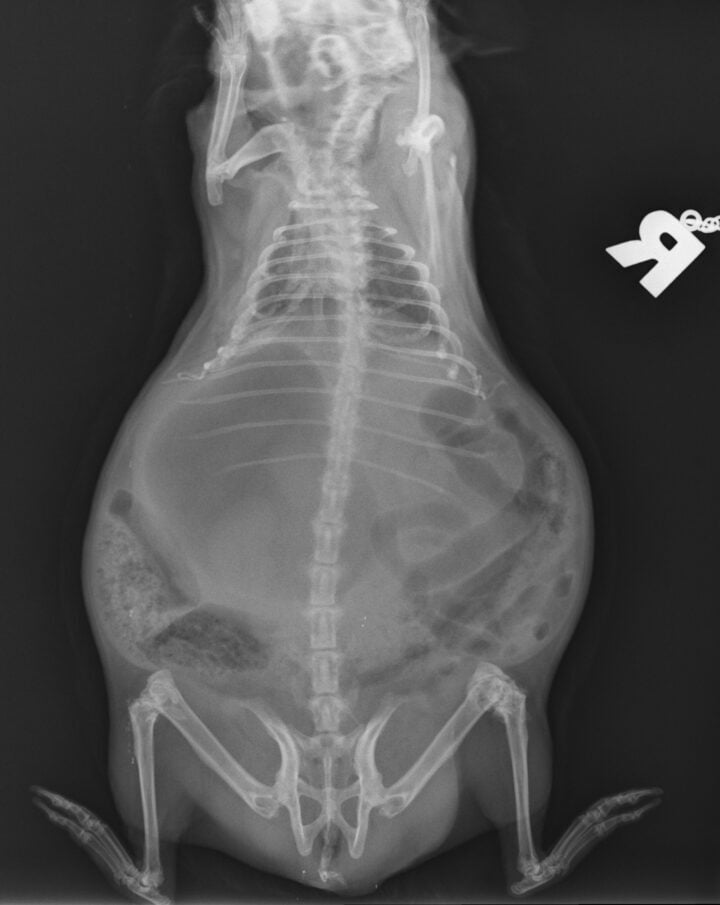

Gastrointestinal obstruction in rabbits is not uncommon, and it is imperative that clinicians are able to differentiate cases of obstruction from cases of gastrointestinal stasis. It is important that obstruction cases are identified early, as intensive treatment must be started swiftly. As rabbits cannot vomit, gastrointestinal contents proximal to the obstruction continue to build, and gas accumulates as the contents ferment, resulting in severe intestinal and gastric tympany; in prolonged cases, this can lead to rupture of the gastrointestinal tract (Figure 1).

Cases of obstruction were more likely to have gastric distension where the sum of the height and length of the stomach was greater than or equal to the length from the first lumbar vertebra to the coxofemoral joint. Ninety-two percent of obstruction cases showed contact between the ventral aspect of the stomach and the ventral abdominal wall. In addition, most obstruction cases showed gastric contents consisting primarily of liquid with a “gas cap” (Figure 3A), whereas gastrointestinal stasis cases showed evidence of normal stomach ingesta (Figure 3B).